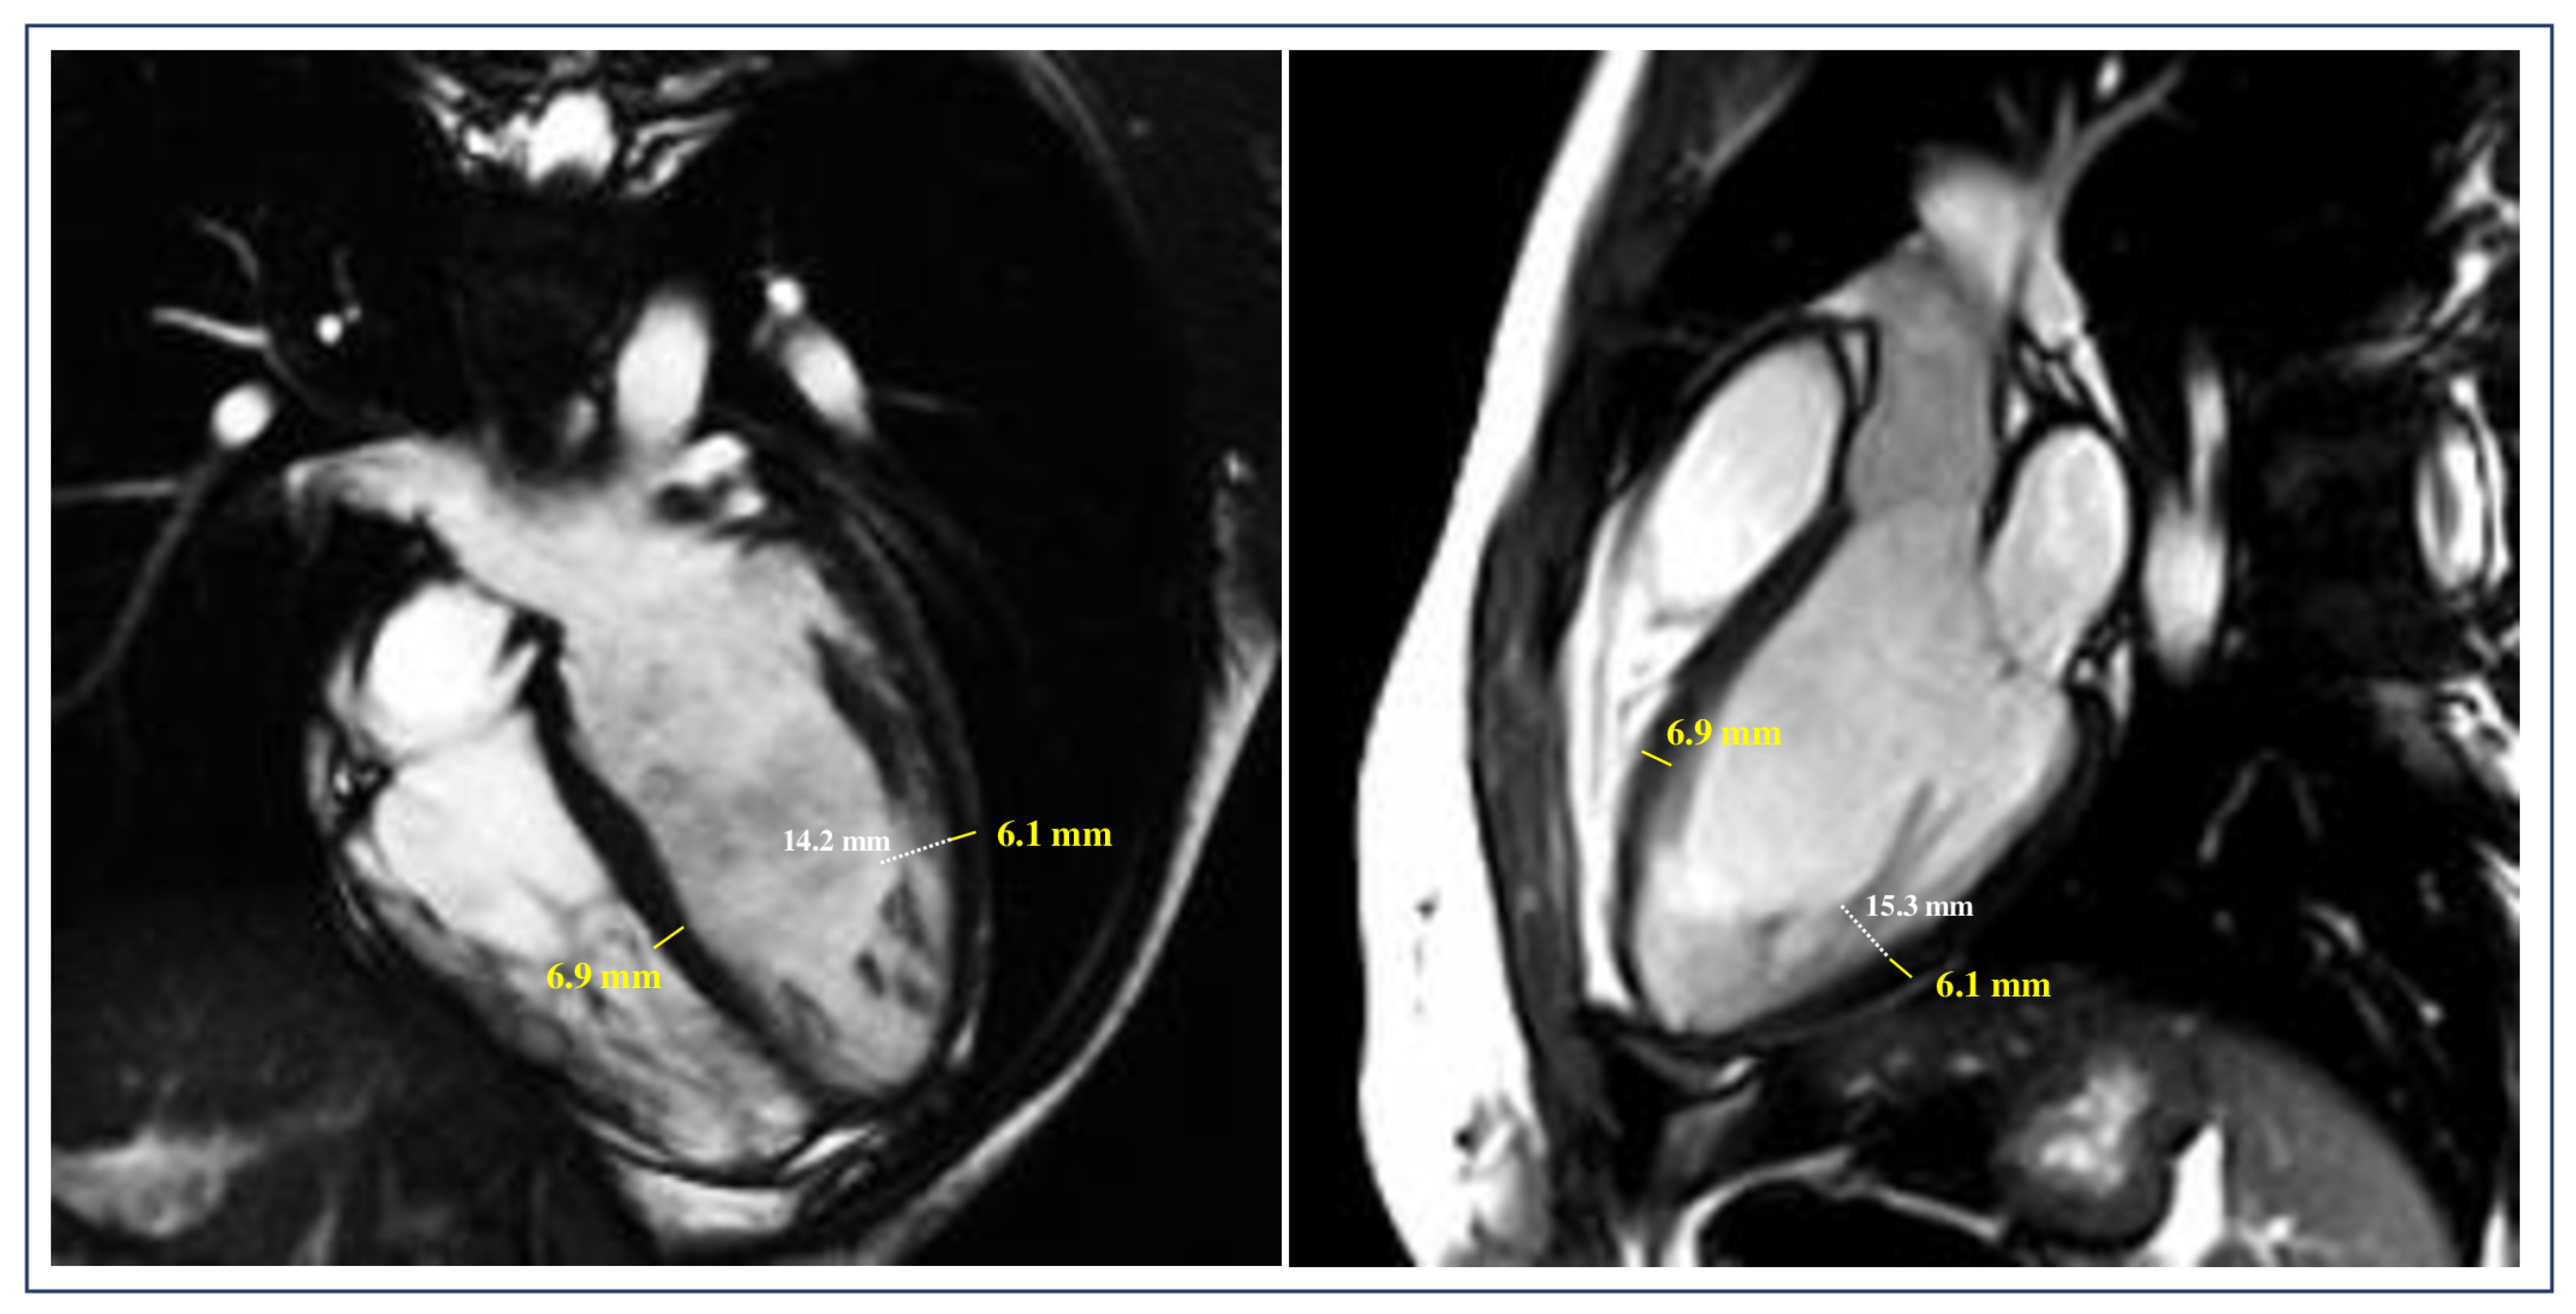

- De Lazzari, M.; Brunetti, G.; Frasson, E.; Zorzi, A.; Cipriani, A.; Migliore, F.; De Conti, G.; Motta, R.; Perazzolo Marra, M.; Corrado, D. Thinning of compact layer and systolic dysfunction in isolated left ventricular non-compaction: A cardiac magnetic resonance study. Int. J. Cardiol. 2024, 397, 131614. [Google Scholar] [CrossRef]